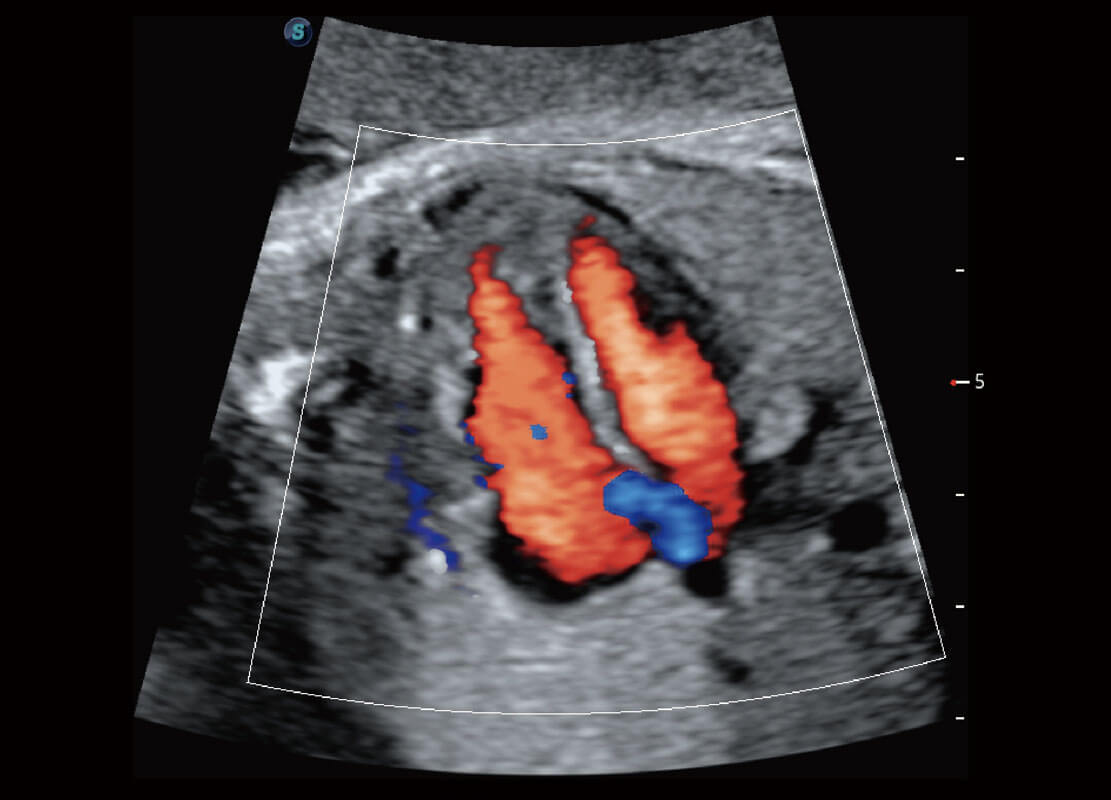

早孕筛查

P60在胎儿早孕期超声筛查中为您带来优异的图像质量。

• 早孕-胎心

• 高分辨率容积成像-早孕胎儿

• 胎儿体循环